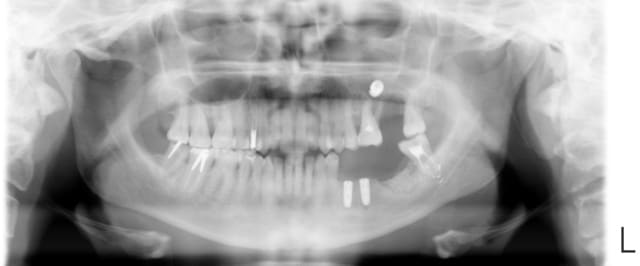

oui, c'est ça: fenêtre latérale et recherche. Mais entre la pano et le retour au fauteuil, je le trouvais plus! d’où la 2eme radio: il avait roulé au fond. du coup, j'ai mis la patiente assise, lui ai fait bouger la tête par quelques petits mouvement bref, ce qui l'a fait se replacer dans le bas fond. avec l'aspi, j'ai pu le ramener et l'attraper.

non, j'ai fini le bas avant d'aller à la peche!

Si effectivement ça peut vous servir, méfiez vous des zones sous sinusienne avec os peu dense et cortical du sinus peu visible: cf pano jointe.